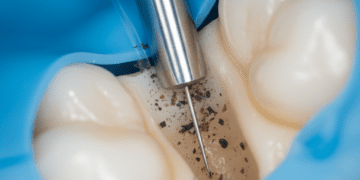

Diferente do desgaste mecânico ou da abrasão dentária, que resulta do atrito ou escovação excessiva, a erosão é caracterizada pela dissolução química dos minerais do esmalte. Inicialmente, a substância mineral do esmalte é removida, deixando a superfície mais frágil e suscetível a outros tipos de desgaste.

O exame clínico permite avaliar visualmente o desgaste e a presença de alterações na superfície dentária. Manifestações típicas de erosão incluem o desgaste em áreas expostas a ácido, como faces palatinas dos dentes superiores em casos de refluxo.

Nos casos mais avançados, a odontologia restauradora oferece opções como resinas compostas, facetas, coroas e outras restaurações que protegem o dente, recuperando forma e função. A escolha do material e técnica depende da extensão da erosão, da localização dos dentes afetados, da estética e da função mastigatória.